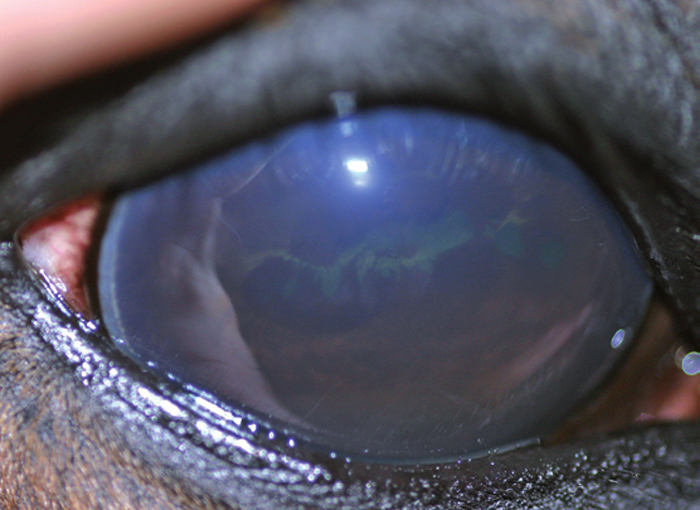

Natural Remedies For Uveitis In Horses . There’s no cure, but it also need not be a death sentence for a horse. treatment of uveitis in horses. Treat the ocular pain and control the inflammation. cotton, suffering from eru. recurrent uveitis is a common cause of blindness in horses. one equine nutritionist offers dietary advice that might help reduce inflammation and guard against gastric. Management and treatment can help preserve sight longer, and even if an eye is removed, many horses can still live normal, active lives and even compete. in cases of uveitis rapid, aggressive treatment is required to reduce the possibility of the horse losing sight in. treatment will take several weeks to months to complete.